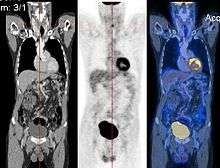

Image registration is a process that searches for the correct alignment of images.[9][10][11][12] In the simplest case, two images are aligned. Typically, one image is treated as the target image and the other is treated as a source image; the source image is transformed to match the target image. The optimization procedure updates the transformation of the source image based on a similarity value that evaluates the current quality of the alignment. This iterative procedure is repeated until a (local) optimum is found. An example is the registration of CT and PET images to combine structural and metabolic information (see figure).